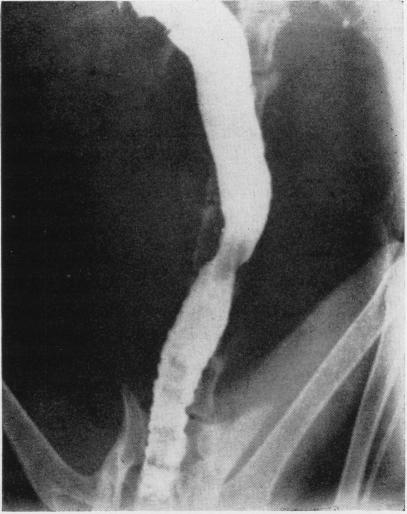

KLINGE F W

Ann Surg. 1952 Jul;136(1):162-6. doi: 10.1097/00000658-195207000-00015.